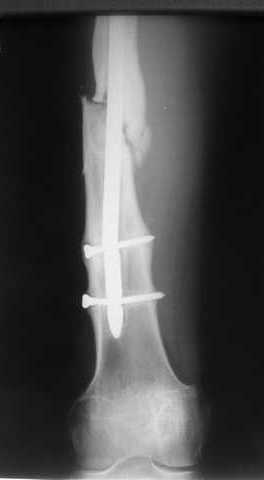

Как обещал, выкладываю рентгенограммы нашего пациента.

Пациенту М., 30-ти лет, 1,5 года назад в одной из московских больниц был выполнен остеосинтез бедренной кости штифтом UFN (диаметр штифта 9 мм).

К нам больной поступил с признаками ложного сустава бедренной кости, перелома

штифта и дистального блокирующего винта (images 1,2,3).

27 марта выполнено удаление блокирующих винтов (сломанный винт пришлось высверливать цапфен-бором), сломанного штифта (дистальный фрагмент удален через канал, образованный разверткой из коленного сустава - image 4),

рассверливание костно-мозгового канала, реостеосинтез штифтом UFN (при проведении штифта в дистальном отломке мы использовали поляризующий винт, диаметр штифта 10 мм). После операции в связи гемартрозом дважды (на 1 и 3 сутки) выполняли пункцию коленного сустава. Сейчас признаков скопления жидкости в полости сустава нет. Послеоперационные рентгенограммы - images 5, 6, 7.